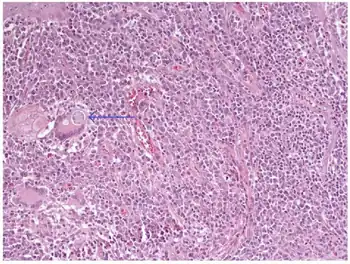

C. immitis can cause a disease called coccidioidomycosis (valley fever).[10][11][12] Its incubation period varies from 7 to 21 days.[13] Coccidioidomycosis is not easily diagnosed on the basis of vital signs and symptoms, which are usually vague and nonspecific. Even a chest X-ray or CT scan cannot reliably distinguish it from other lung diseases, including lung cancer. Blood or urine tests are administered, which aim to discover Coccidioides antigens. However, because the Coccidioides creates a mass that can mimic a lung tumor, the correct diagnosis may require a tissue sample (biopsy). A Gomori methenamine silver stain can then confirm the presence of the Coccidioides organism's characteristic spherules within the tissue. The C. immitis fungus can be cultured from a patient sample, but the culture can take weeks to grow and requires special precautions on a part of the laboratory staff while handling it (screw cap vials and sterile transfer hoods are recommended).[14] It is reported as the tenth-most often acquired infection in the laboratory conditions with two documented deaths.[2] Until October 2012, C. immitis had been listed as a select agent by both the U.S. Department of Health and Human Services and the U.S. Department of Agriculture, and was considered a biosafety level 3 pathogen.

Septate hyphae of Coccidioides immitis with 90 degree branching and thick walled barrel shaped arthroconidia alternating with empty cells